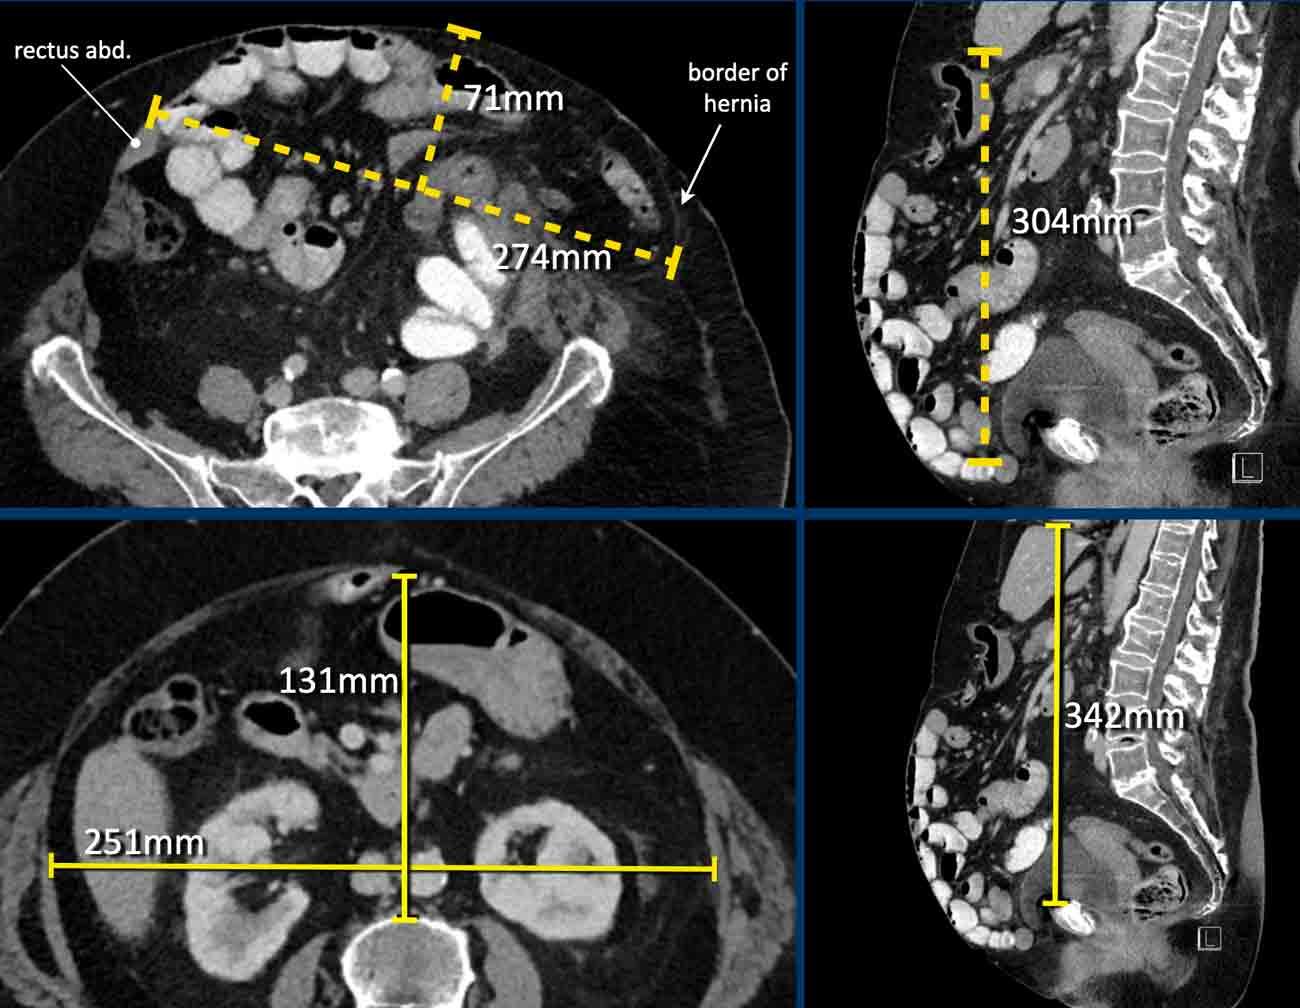

Hình ảnh

Ở bệnh nhân này, mức độ mất vùng chứa > 20% và cần áp dụng các chiến lược bổ sung để tăng dung tích và độ giãn nở của khoang bụng.

Ở bệnh nhân này với khối thoát vị, các số đo như sau:

- Thể tích túi thoát vị (HSV) = (203 x 85 x 125 mm x 0,52) x 10-6 = 1,12 lít.

- Thể tích khoang bụng (ACV) = (297 x 100 x 328 mm x 0,52) x 10-6 = 5,1 lít.

- Tổng thể tích phúc mạc (TPV) = ACV + HSV = 5,1 + 1,12 = 6,2 lít.

Mức độ mất vùng chứa = 1,12 / 6,2 x 100% = 18%